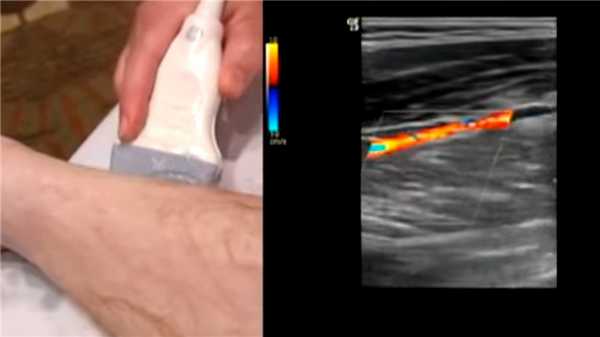

Допплеровское ультразвуковое исследование

Ультразвуковое исследование самый распространенный метод диагностики. Это исследование - первый шаг к изучению заболеваний сосудов человека. На основе результатов УЗИ строится дальнейший план диагностики и лечения.

Важно: Перед процедурой УЗИ запрещено курить. Курение вызывает сужение сосудов, что ведет к получению неправильных результатов исследования. Да и в целом перед любой диагностикой и сдачей анализа стоит заранее узнать у врача, как подготовиться. Это поможет избежать неприятных ситуаций на приеме.

Примерно так проходит УЗИ ступни. Источник: Vascular Online Training VOT / YouTube

С помощью УЗИ удается рассмотреть все изменения сосудов, степень их сужения или наличие стеноза. Определить локализацию и длительность атеросклеротических процессов.